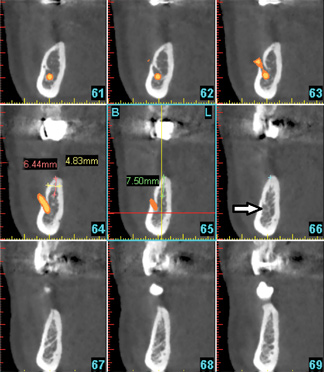

Fig 5. Anterior loop of the mental foramen: six consecutive cross-sectional views. Sections anterior to the mental foramen demonstrate a radiolucency that corresponds to the loop of the inferior alveolar nerve. In these cross-sections, the anterior loop has a “C” shape due to the cut of the images (arrow). Therefore, immediately above the loop, an implant longer than the safety zone (distance from the alveolar ridge to the mental foramen minus 2 mm for safety) should not be placed.

Figure 5

Fig 6. No anterior loop of the mental foramen: nine consecutive cross-sectional views. Sections anterior to the mental foramen do not demonstrate any radiolucency that corresponds to the loop of the inferior alveolar nerve. Arrow is pointing to the bone anterior to the mental foramen, which does not demonstrate a loop.

Figure 6